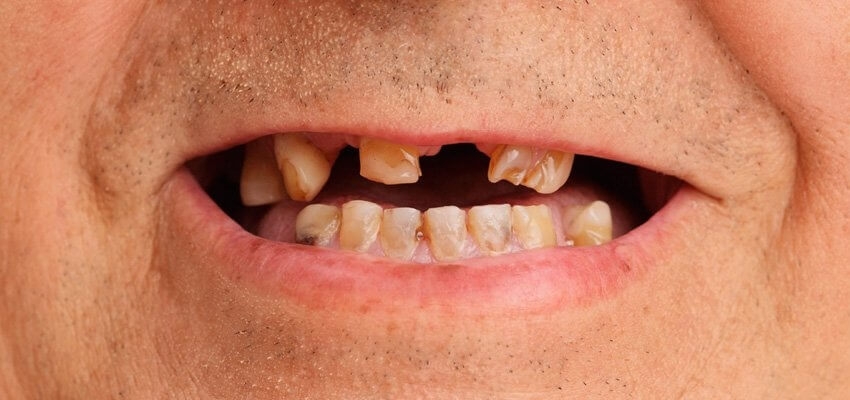

Consequência do refluxo na saúde bucal:

Erosão dentario devido à acidez do suco gastrointestinal, podemos afirmar que uma perda progressiva e irreversível da estrutura dental, tornando os dentes sensíveis a estímulos térmicos (frio, quente e ao ar ), táteis, amarelados, boca seca (xerostomia), devido à diminuição e quantidade do fluxo salivar, consequentemente aumento de aftas, doença periodontal e halitose. Normalmente, a procura por um cirurgião dentista é realizada após a evolução dos desgastes dentários provenientes da erosão, onde a necessidade de reabilitações mais invasivas, como tratamento endodônticos (canal), coroas, facetas, já estão indicadas para devolução da forma, textura e comprimento dos dentes como do terço inferior da face em casos mais avançados, do contrário a perda dentária será inevitável. O refluxo gastroesofágico tem tratamento. Caso sofra desse mal, procure o gastroenterologista para tratar o refluxo e um cirurgião dentista para tratar as consequênciais bucais. Afinal, não deixe que esse doença acabe com seu prazer de sorrir, falar e se apresentar.